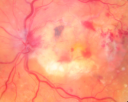

87-year-old woman I saw in the office on February 8, 2008. She has had age-related macular degeneration in both eyes for some time with disciform scars. She takes a baby aspirin about every other day. She has noticed over the last month or two decreased vision in her left eye. She also has had borderline glaucoma for some time.

VISUAL ACUITY: OD: 20/200, OS 20/400. IOP: OU 19.

OD: Vertical C/D ratio is 0.3. There is an atrophic macular scar 3 disc diameters across.

OS: Vertical C/D ratio is 0.1. There is 3+ optic nerve edema. There is a posterior vitreous separation. There is an atrophic macular scar 3 disc diameters across. There is also dilated retinal veins in all four quadrants with retinal hemorrhage in all four quadrants.

OCT SCAN: The OCT scan of the right eye shows retinal atrophy. The left eye shows retinal atrophy with macular edema predominately nasal to the fovea.

FLUORESCEIN ANGIOGRAM: FA of the left eye shows poor circulation with the re-circulation time of almost 20 seconds, which normal being less than 4 seconds. In the left eye there is also late leakage from the macular vessels. The perfusion in the periphery looks pretty good. I do not see greater than 10 areas of non-perfusion. The right eye has hyperfluorescence corresponding to the macular scar.

1. AGE-RELATED MACULAR DEGENERATION – BOTH EYES

2. CHRONIC MACULAR SCARS – BOTH EYES

3. NEW CENTRAL RETINAL VEIN OCCLUSION WITH MACULAR EDEMA AND OPTIC NERVE EDEMA – LEFT EYE